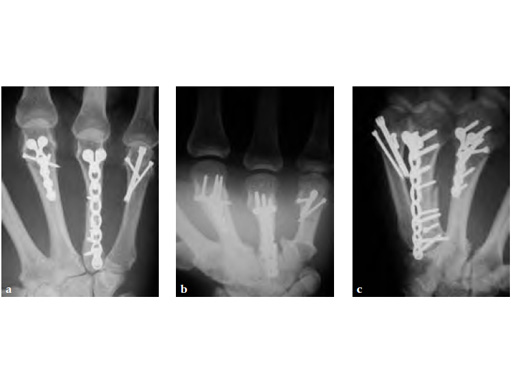

Periarticular complex metacarpal fracture treated with 1.5 LCP modular hand system and 1.5 headless compression screw.

Fig 2ac Postoperative.

Case provided by Tom Fischer, Indianapolis, USA